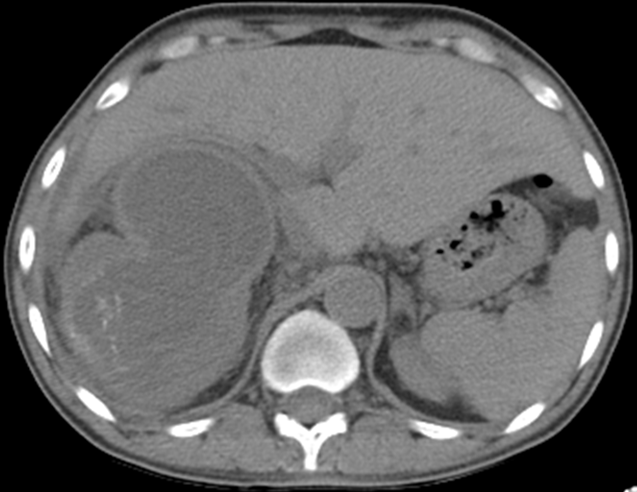

L'hydatidose est une parasitose liée au développement de la forme larvaire d'Echinococcus granulosus. Le kyste hydatique rénal constitue une localisation inhabituelle. Il peut se fistuliser dans les voies excrétrices urinaires et nécessiter alors une prise en charge spécifique. Nous présentons ici un cas témoignant de la spécificité diagnostique et thérapeutique de cette pathologie chez les patients en hémodialyse chronique, chez qui la diurèse n’est pas toujours conservée pour témoigner de l’hydaturie et orienter le diagnostic. Il s’agit donc d’un patient de 47 ans, en hémodialyse depuis 4 ans pour une néphropathie glomérulaire découverte au stade terminal. Le patient présente depuis 6 mois une altération de l’état général avec des lombagies droites, sans fièvre. La TDM abdominale montre un rein droit mesurant 13,4cm, siège d’une importante dilatation urétéro-pyélo-calicielle laminant le parenchyme rénal, avec un pyélon mesuré à 4,3cm, sans obstacle lithiasique visible. Cependant on individualise au niveau polaire inférieur droit, une formation kystique contenant des membranes, mesurant approximativement 76,5 x 54mm, communiquant avec le pyélon qui contient également quelques membranes. Un interrogatoire plus laborieux a révélé la présence d’une hydaturie sur les quelques gouttes de diurèse résiduelle. Vu que le patient est en insuffisance rénale chronique terminale en traitement de suppléance, le choix thérapeutique s’est porté sur une néphrectomie totale.